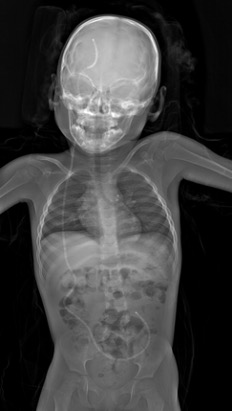

Klinik Görüntüler

Yukarıdaki örnek görüntüler, Lodox Xmplar-dr sisteminin her yaş ve vücut tipindeki hastalarda sunduğu yüksek çözünürlüklü tam vücut görüntüleme kapasitesini göstermektedir. Pediatrik hastalardan erişkinlere, düşük kilolu bireylerden yüksek vücut kitle indeksine sahip hastalara kadar geniş bir hasta grubunda net anatomik detay elde edilebilmektedir. Linear slot-scanning teknolojisi sayesinde kemik, yumuşak doku ve yabancı cisimler tek çekimde, ortalama 13–16 saniyede ve ultra düşük radyasyon dozu ile görüntülenir. Bu özellik, özellikle travma ve acil servis koşullarında hem hızlı tanı koymayı hem de radyasyona bağlı riskleri en aza indirmeyi mümkün kılar.